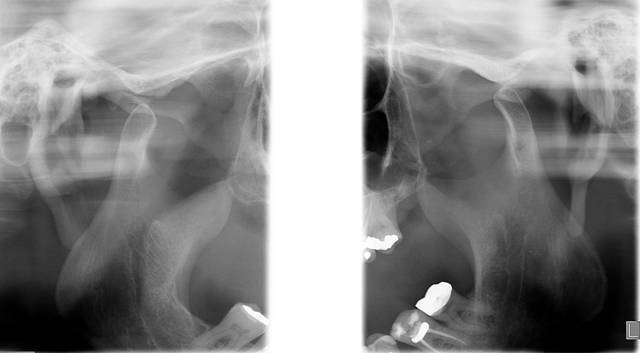

PLANIGRAFIA DE ATM

Tem a finalidade de melhor evidenciar o processo condilar em duas posições: abertura máxima (AM) e máxima interdigitação cuspidária (MIC), em ambos os lados. É especifica para análise da estrutura condilar.

* Boca Aberta

* Boca Fechada